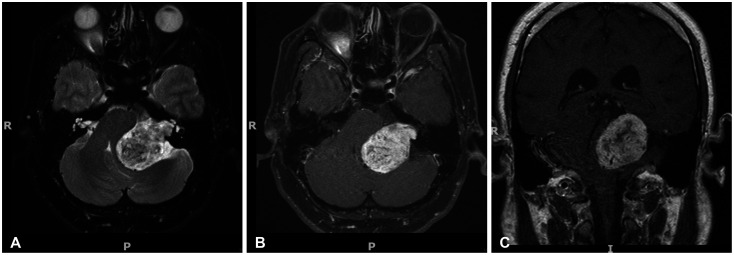

前庭分裂瘤(VS)是最常见的小脑肿瘤。对较小尺寸的 VS(30 毫米)的自然史尚未进行广泛研究,这主要是因为它们非常罕见。因此,大多数患者都会接受传统的手术治疗,而手术会带来很大的神经系统发病风险。在此,我们报告了一例 30 岁男性的巨大 VS(>40 毫米)患者,该患者自发消退。他失去随访机会长达 18 年之久,再次就诊时症状明显改善,重复造影显示肿瘤明显缩小。参考其他研究中的类似病例,我们推测大多数大型和巨型 VS 都会经历一个生长和停滞阶段,随后由于致瘤因素和消退因素之间的平衡发生变化而消退。结合新出现的分子数据,我们需要开展进一步研究,以更好地了解大型和巨型 VS 的病史,从而制定更加个性化的治疗方案。这可能包括将非手术治疗作为一种可行的选择。

Vestibular schwannomas (VSs) are the most common cerebellopontine tumors. The natural history of smaller-sized VSs (<30 mm) has been well-studied, leading to the recommendation of a "watch and wait" approach. However, large VSs (>30 mm) have not been extensively studied, mainly because of their rarity. As such, most patients are conventionally offered surgery which carries a significant risk of neurological morbidity. Here, we report a case of a giant VS (>40 mm) in a 30-year-old man who regressed spontaneously. He was lost to follow-up for 18 years and, upon re-presentation, the symptomatology drastically improved and repeat imaging demonstrated a marked reduction in tumor size. Referring to similar cases in other studies, we postulate that most large and giant VSs undergo a phase of growth and stasis, followed by regression due to shifts in the balance between tumorigenic and regressive factors. Taken together with emerging molecular data, further studies are required to better understand the history of large and giant VSs to shape more personalized treatment options. This potentially includes non-operative management as a tenable option.